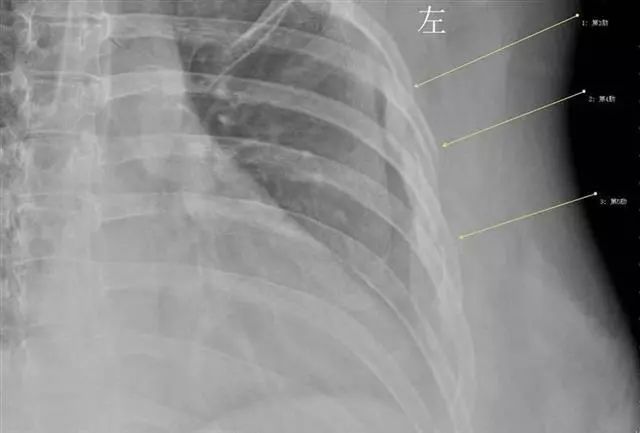

当拍片结果出来后,胸外科医生都不敢相信,肋骨竟然断了三根(第3、4、5肋骨骨折)。胸外科医生给她上了胸带固定,并给予了止咳镇痛的药物治疗。胸外科徐家行医生详细询问病史,在排除了其他因素后,考虑还是咳嗽引起的肋骨骨折。